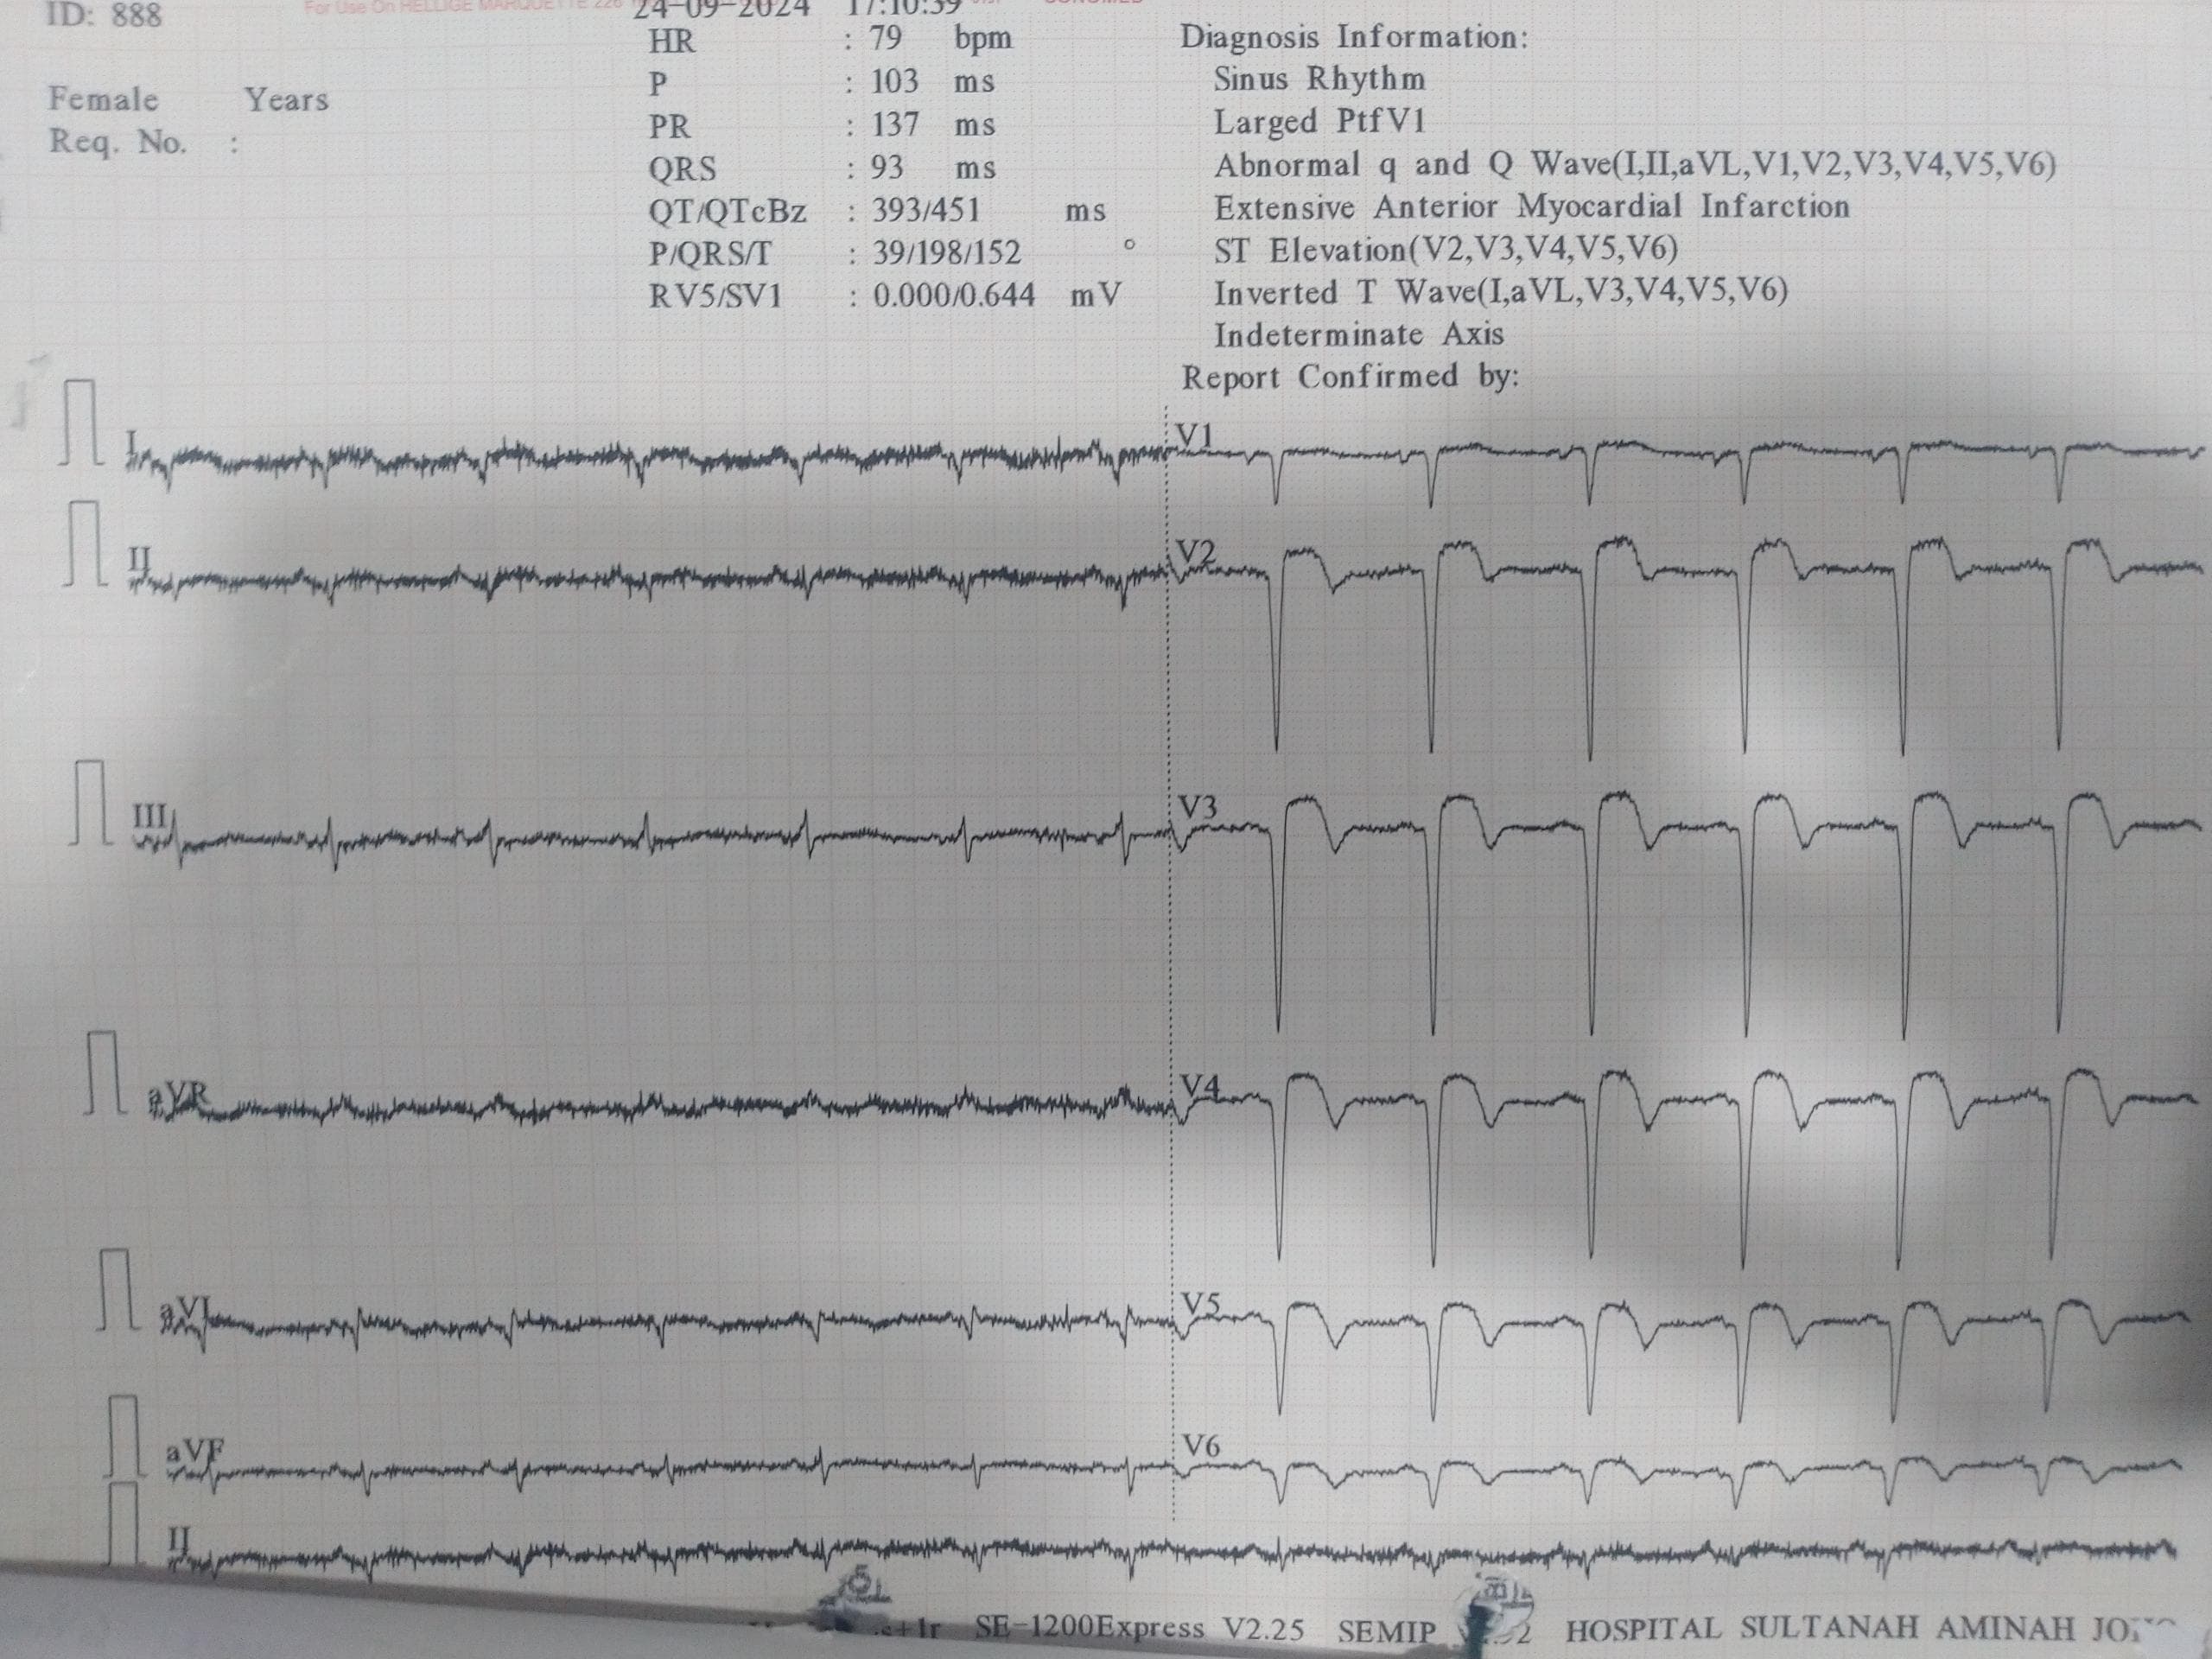

Relevant Test Results Prior to Catheterization

His electrocardiogram on admission showed sinus rhythm with deep Q wave over lead V1 to V6 with ST elevation of 3mm. His Trop T was 78454 ng/L and creatinine kinase was 692 U/L. His lactate dehydrogenase was 1256 U/L. He had mild acute kidney injury with creatinine level of 114 micromoles/L. His total cholesterol was 4.5mmol/L and low density lipoprotein was 2.8 mmol/L. The fasting blood glucose level was 3 mmol/L. Otherwise, the liver function test and electrolytes levels were unremarkable.